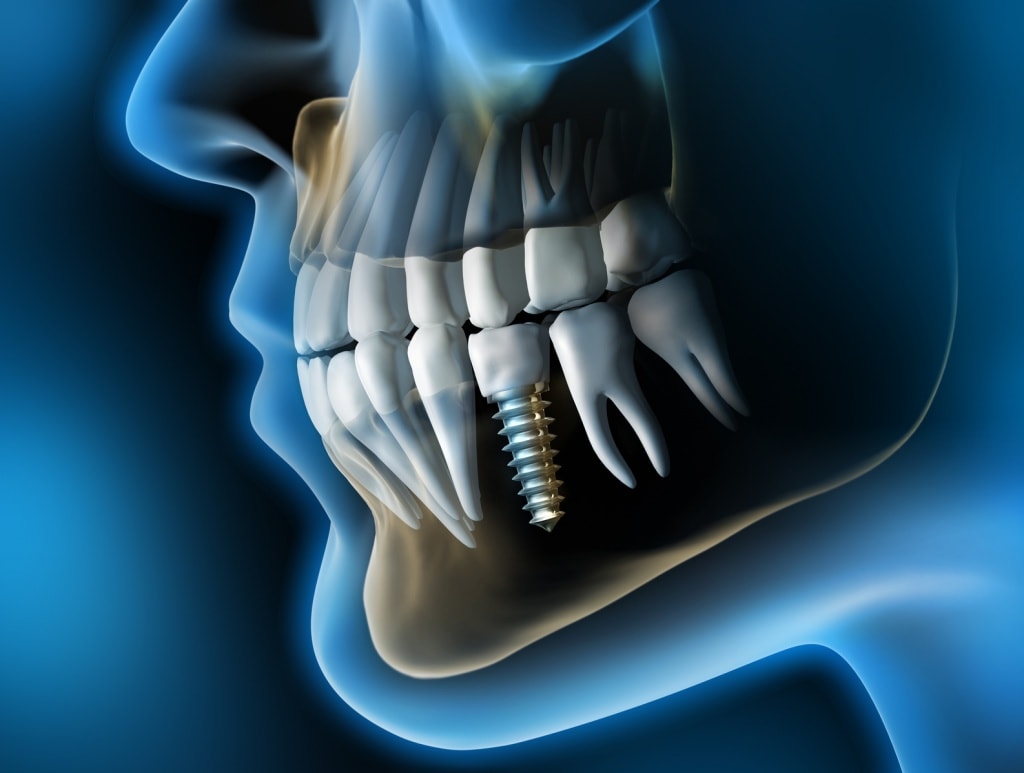

Дентальная имплантация - это хирургическая манипуляция по установке титанового имплантата в костную ткань верхней или нижней челюсти для последующего на нём протезирования.

Хирургический этап

Для выполнения дентальной имплантации производится местная анестезия. Делается разрез десны в области отсутствующего зуба, отодвигается десна. В костной ткани препарируется ложе для имплантата, затем устанавливается имплантат с необходимым усилием. В имплантат устанавливается заглушка, затем накладываются швы. После операции выполняется контрольная рентгенограмма.Вся операция при стандартных условиях занимает не более 30-40 минут.